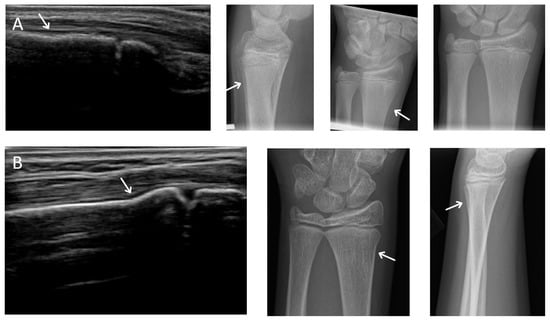

The “combined reader” produced 4 false positives which were individually reviewed by the radiologist. Two scans were misclassified due to 3DUS artifacts and the other two scans represented possible subtle fractures that were not identified on radiographs (Figure 1). The combined reader did not have any false negatives (Figure 2).

There were 2 possible radiographic false negatives out of 10 negative radiographs, as the US revealed subtle cortical irregularities that could represent undisplaced fractures. Retrospective review of two X-rays in light of ultrasound findings showed subtle cortical contour irregularities that might have represented the fractures identified on US (Figure 3). Previous studies had also reported the possibility that ultrasound may identify subtle fractures not seen on radiographs [7]. The clinical significance of these possible undisplaced fractures is unknown. Future study could potentially perform limited MRI in this small subset of patients with discrepant ultrasound/X-ray findings to clarify vs. an external gold standard.

Figure 1. Possible missed fractures. (A,B) are dorsal longitudinal views of the distal radius of two possible X-ray false negatives. Note the excess angulation of the distal radius may represent torus fractures. The possible defect is observable on X-ray.